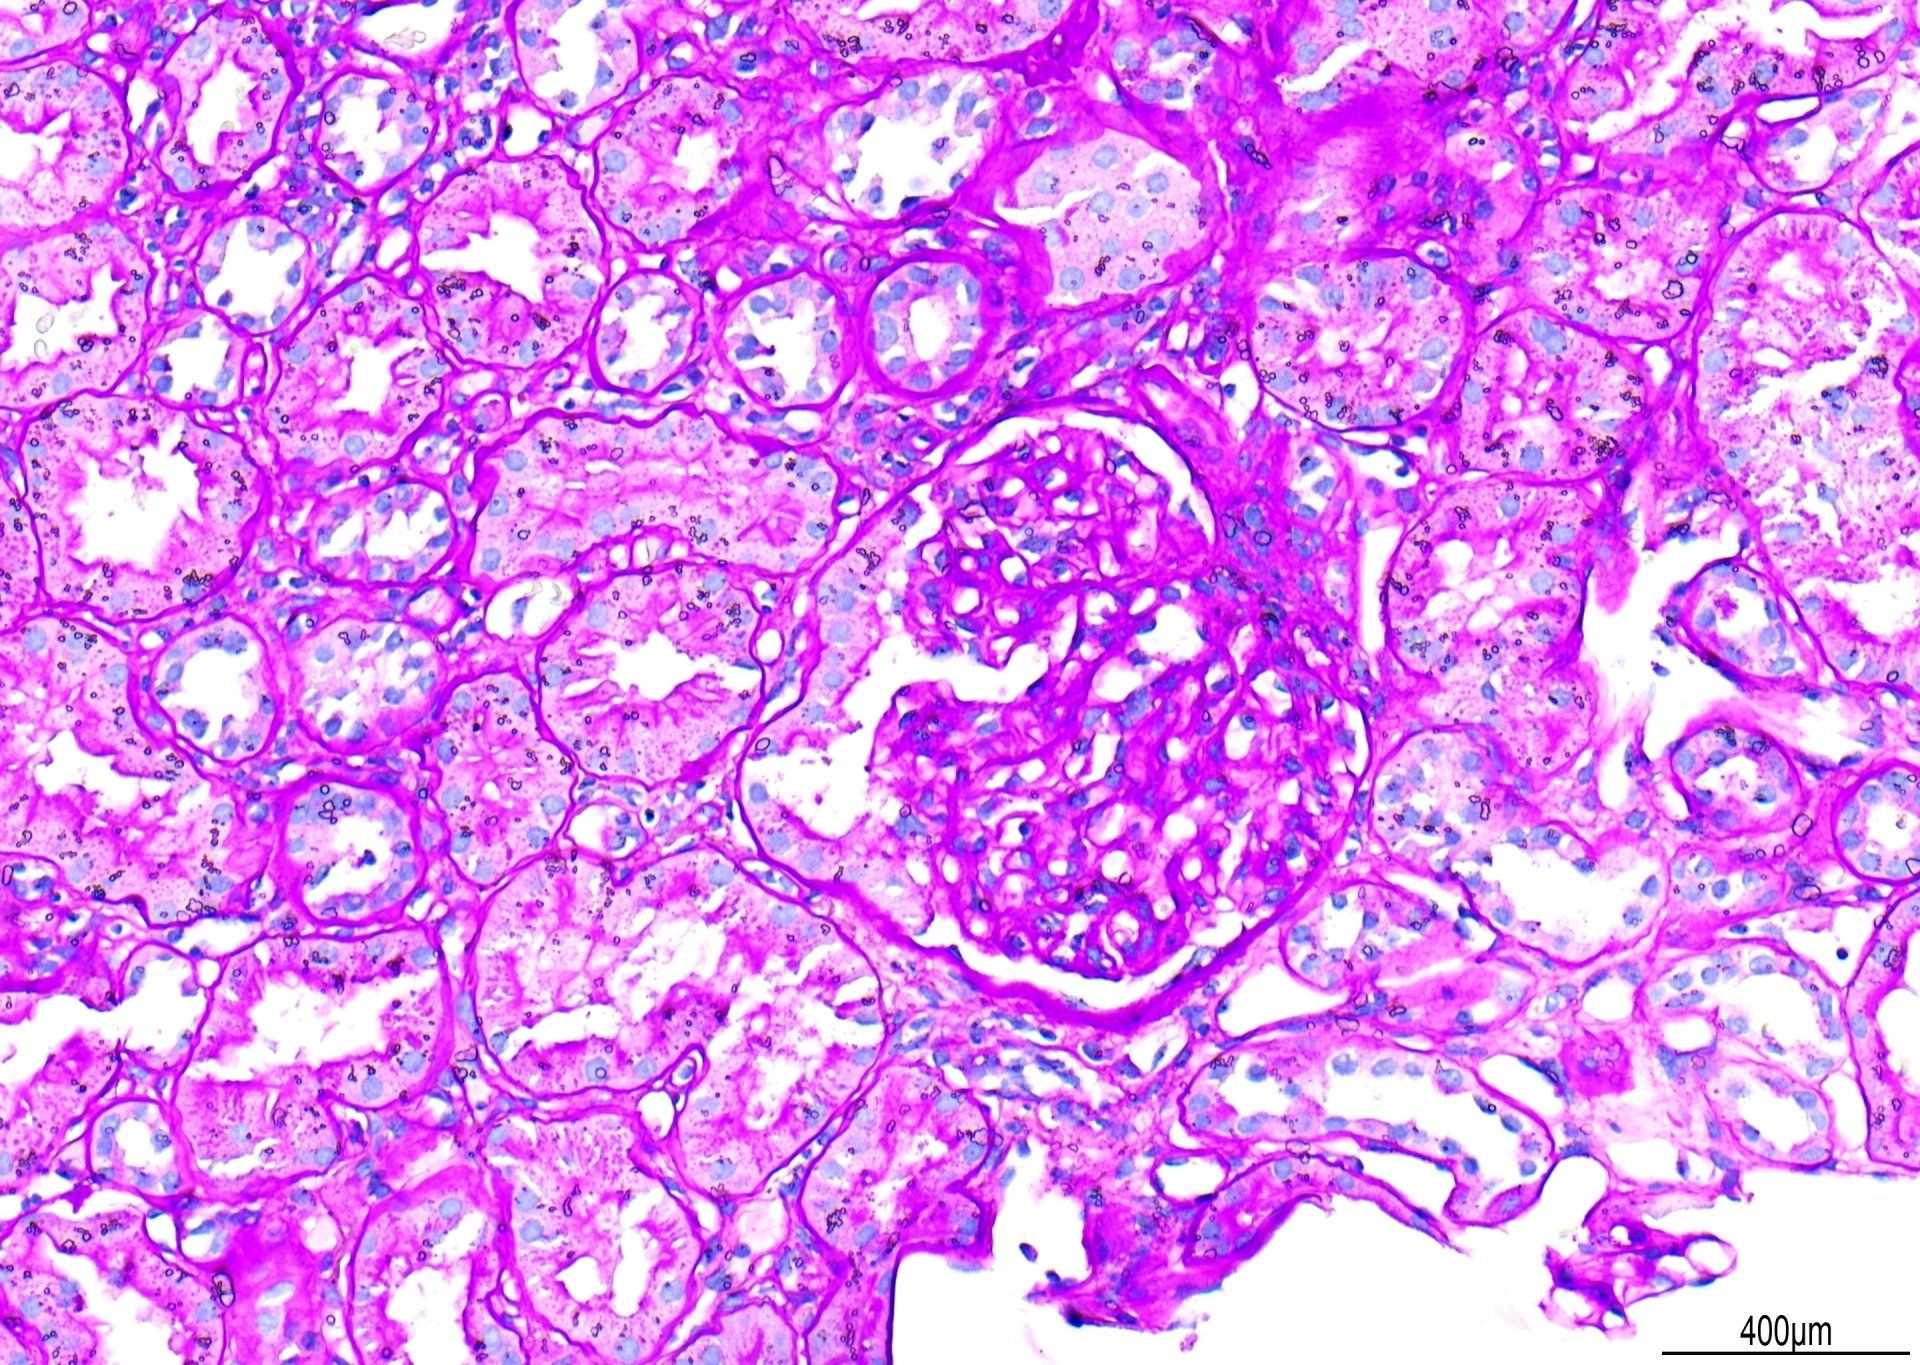

PAS - Nyreordning

Set ved x20 er dette et eksempel på en PAS-farvning. Der blev trukket point fra for 'primær baggrundsfarvning'. Selvom de glomerulære basalmembraner er godt farvede, kunne kontrasten være bedre, hvis der var mindre Schiff-baggrundsfarvning. Derudover blev der set vanddråber under dækglasset. Den samlede score for dette afsnit var 7/10.